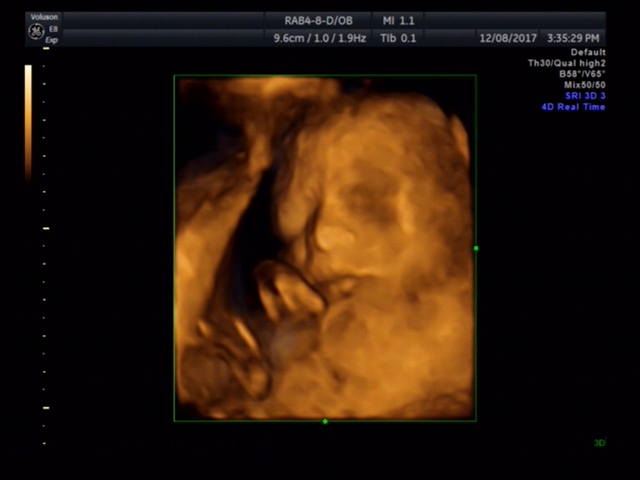

JESSICA👣

宝宝3个月12天

孕12周+4天

鼻子应该很高,好看^_^

JESSICA👣[帖主]:医生说鼻子很像我是个高鼻梁水滴鼻,嘴唇的轮廓也有点像,其他就不清楚了。